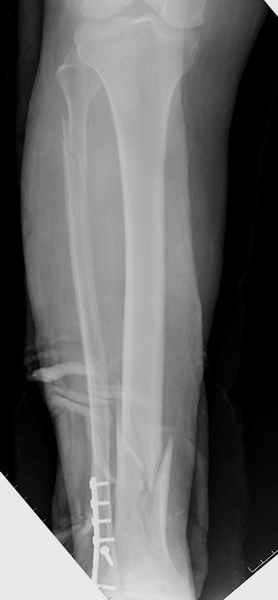

У меня молодой врач на линии, снимки отправил через эл. почту,

спрашивает что делать с больным который поступил недавно, фермер 55 лет падение при пьяной драке в баре, года два назад перенес операцию на лодыжке, на снимках и КТ перелом без вовлечения сустава,

Повреждение такой локализации, на которой применимы и аппарат (классический Илизарова или гибридный), пластина, особенно Locked Plate, и гвоздь с блокированием. В нашей клинике был бы выполнен закрытый интрамедуллярный остеосинтез. Желательно использовать гвоздь с возможностью провести более чем 2 обычных фронтальных винта в дистальном отломке.

Здесь мы использовали новый Synthes Nail с дополнительными дырками, в проксимальной части 4: по две косых и поперечные (один стандартный а другой динамический), в дистальной части две поперечные, прямая и косая. Вес больного более 120 кг, нагрузку начнем через месяц.

Получилось красиво, поздравляю. Вверху можно было ограничиться одним винтом во фронтальное статическое отверстие, зачем два 45-градусных?

При такий спирали задний край tibia может быть сломан - нет ли этого в данном случае? На всякий случай можно было ввести 1-2 винта 4,5 мм спереди назад мимо гвоздя. Хотя самый дистальный блокирующий винт, возможно, зацепил этот отломок. А какой тут диаметр гвоздя и locking винтов?